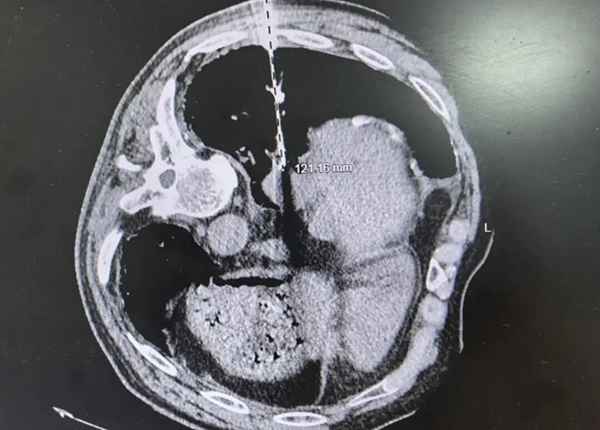

近日,周老伯来到南通六院肿瘤科就诊。复查胸部CT发现:短短三个月,结节竟增大至2.9cm*2.4cm,体积翻了超过一倍!更糟糕的是,进一步检查提示已发生骨转移及纵膈淋巴结转移,病情进展极为迅速。

结节位于右下肺,位置极深,藏匿于肝脏与心脏的“夹缝”之间,靠近膈肌,位置变化受呼吸运动影响大,进针路径稍有不慎,便可能误伤重要脏器,引发大出血。

在CT精准引导下,马雷副主任医师操作超长穿刺针,巧妙避开心脏、大血管及肝脏,精准抵达病灶核心,顺利完成组织取材。